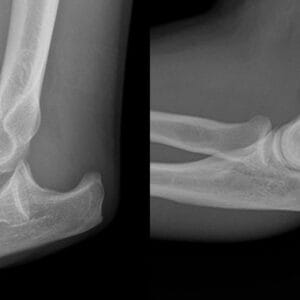

Arm Patient informationPreparing for arm surgery, whether for conditions like fractures, ligament tears, or nerve issues, is a crucial step to ensure a smooth procedure and optimal recovery. Knowing what to expect before, during, and after the surgery can help reduce anxiety and improve outcomes. Key Steps to Prepare for Arm Surgery